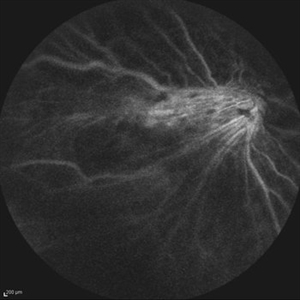

Idiopathic Retinitis, Vasculitis, Aneurysms, and Neuroretinitis (IRVAN) Idiopathic Retinitis, Vasculitis, Aneurysms, and Neuroretinitis (IRVAN)Nov 13 2013 by Hamid Ahmadieh, MD Wide-field late phase FA image of the left eye of a 35-year-old woman with idiopathic retinitis, vasculitis, aneurysms, and neuroretinitis (IRVAN). Large areas of capillary non-perfusion are visible temporally. Photographer: Solmaz Shahmohammad , Negah Eye Center , Tehran Imaging device: Heidelberg Spectralis Condition/keywords: aneurysm, neuroretinitis, retinal vasculitis, retinitis